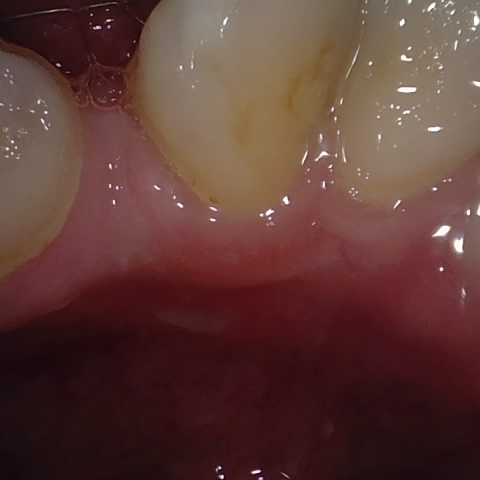

Image 55 / 400

NHD20738

Annotated as "Bad"

Original Image Rendering Image